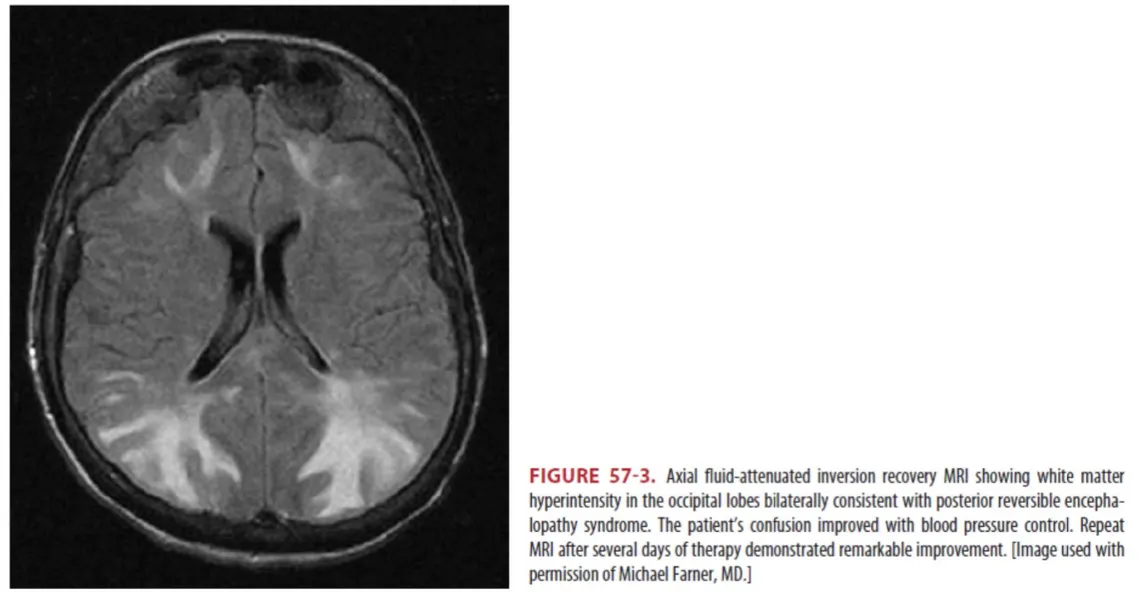

Posterior reversible encephalopathy syndrome (PRES)

: 고혈압성 Vasogenic cerebral edema에 의한 현상

: Brain MR에서 posterior lobe에 reversible edema가 특징적이다